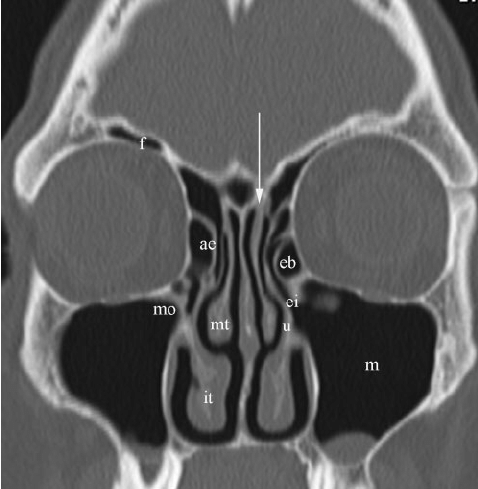

Immediately after vacation and I was cleared of covid, I went in for another CT scan. My scan showed significant issues in all of my sinus cavities. Most completely, if not almost completely filled with infection and swollen tissue. The nasal swab done before vacation had come back as positive for two different types of staph infections in my ethmoid sinuses and nasal cavity. I received word a few days later that the sample began to grow mucor fungus, which is most likely causing so many issues in my nose and throat right now. Four different types of oral medications and three different types of sinuses rinses later, and I’m still having issues. Luckily I only have to tolerate the headaches and pressure for a few more days until you guessed it……ANOTHER SINUS SURGERY!

As you can see by my CT above, I’m pretty screwed up when it comes to the sinus department. I am optimistic that Dr. Rizzo will get me all fixed up and hopefully will send me to a great sinus specialist at Jefferson Hospital in Philadelphia. Time will tell how long I will stay healthy and how well the surgery will go, but we will see by next week. Hoping for quick healing and positive vibes, please! ❤️